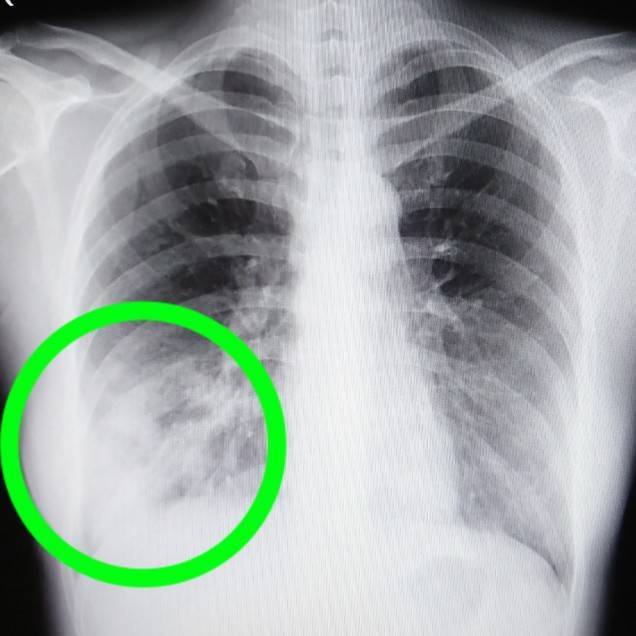

答えはココです。

レントゲンでは見慣れないとなかなか見つけづらいですよね。

肺はいくつかの区域に分かれています。

右肺は大きく3つ(上葉、中葉、舌葉)

左肺は大きく2つ(上葉、下葉)

左肺は心臓もあるので少し狭くなっています。

そして更に伸びている気管支によって合わせて10個ほどの区域に分かれます。

もう一度、先程のCTを見てみると汚い部分がくっきりと限局しているのがわかります。

このような肺炎を区域性肺炎といいます。

肺がんの場合は浸潤していくので肺の区域に関係なく大きくなっていきます。